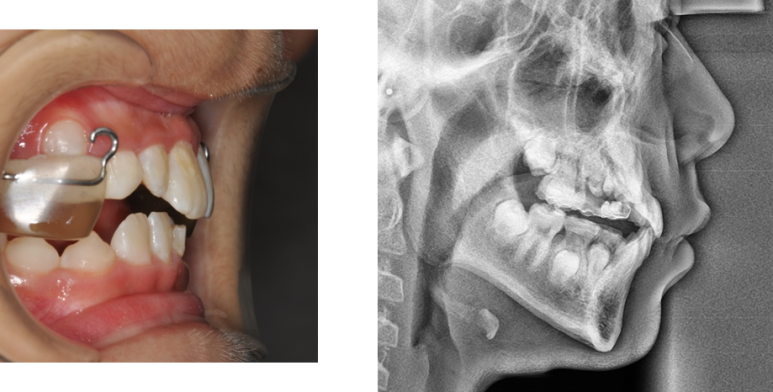

환자분께서는 아이의 치아가 반대로 물려서 내원을 해주셨습니다.

반대교합과 함께 아래턱이 위턱보다 더 나와있는

주걱턱이 함께 있어 성장교정을 진행했습니다.

악궁확장장치와 페이스마스크 장치를 이용하여

위 턱을 넓히고 위 턱을 앞으로 끌어내 주며

아래턱이 나오는 힘을 위 아래로 분산시켜 줍니다.

그러면 이렇게 반대교합도 해소하고,

위 아래 턱의 조화도 맞출 수 있게 되었습니다.